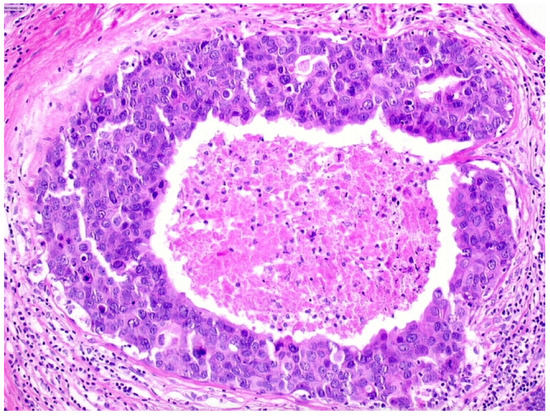

We observed that 503 patients received the diagnosis of DIN3 (high-grade DCIS, Figure 4)—19.9% (100/503) of them were upgraded to invasive cancer. The overall mean diameter of the DIN3 lesions was 25 mm.

We reported, post-VABB, complete removal of the lesion in 206 out of 503 patients with DIN3 diagnosis. Among them, we reported 23 cases of invasive carcinoma on surgical specimen, and thus 11.2% (23/206) of high-grade DCIS cases with no residual lesion were upgraded to invasive cancer.

Patients with diagnosis of high-grade DCIS showing complete removal of the lesion experienced a significantly lower upgrade rate compared to those showing mammographically detectable residual tumor after VABB (p-value < 0.05).

Figure 4. Ductal carcinoma in situ of high nuclear grade with central necrosis (DIN3).